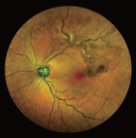

1956年,ICGA 首先被使用于心功能和肝臟的功能檢查。1995年Bishoff等研制了可以FFA和ICGA同步進(jìn)行的眼底照相設(shè)備,得到了高分辨率、大廣角的圖像,結(jié)合計(jì)算機(jī)技術(shù)的應(yīng)用,可以得到三維組合的眼底圖像。

ICGA主要用于觀察脈絡(luò)膜的血管結(jié)構(gòu)和循環(huán)特點(diǎn),揭示脈絡(luò)膜循環(huán)的細(xì)節(jié),是目前PCV診斷的“金標(biāo)淮“。且由于吲哚青綠染料具有與熒光素鈉不同的特性,所以能更加直觀地了解脈絡(luò)膜血管循環(huán)狀態(tài),可彌補(bǔ)FFA檢查看不清脈絡(luò)膜循環(huán)的不足,在某些特殊情況下可協(xié)助FFA對(duì)視網(wǎng)膜血管性疾病診斷作出補(bǔ)充。

ICGA影像